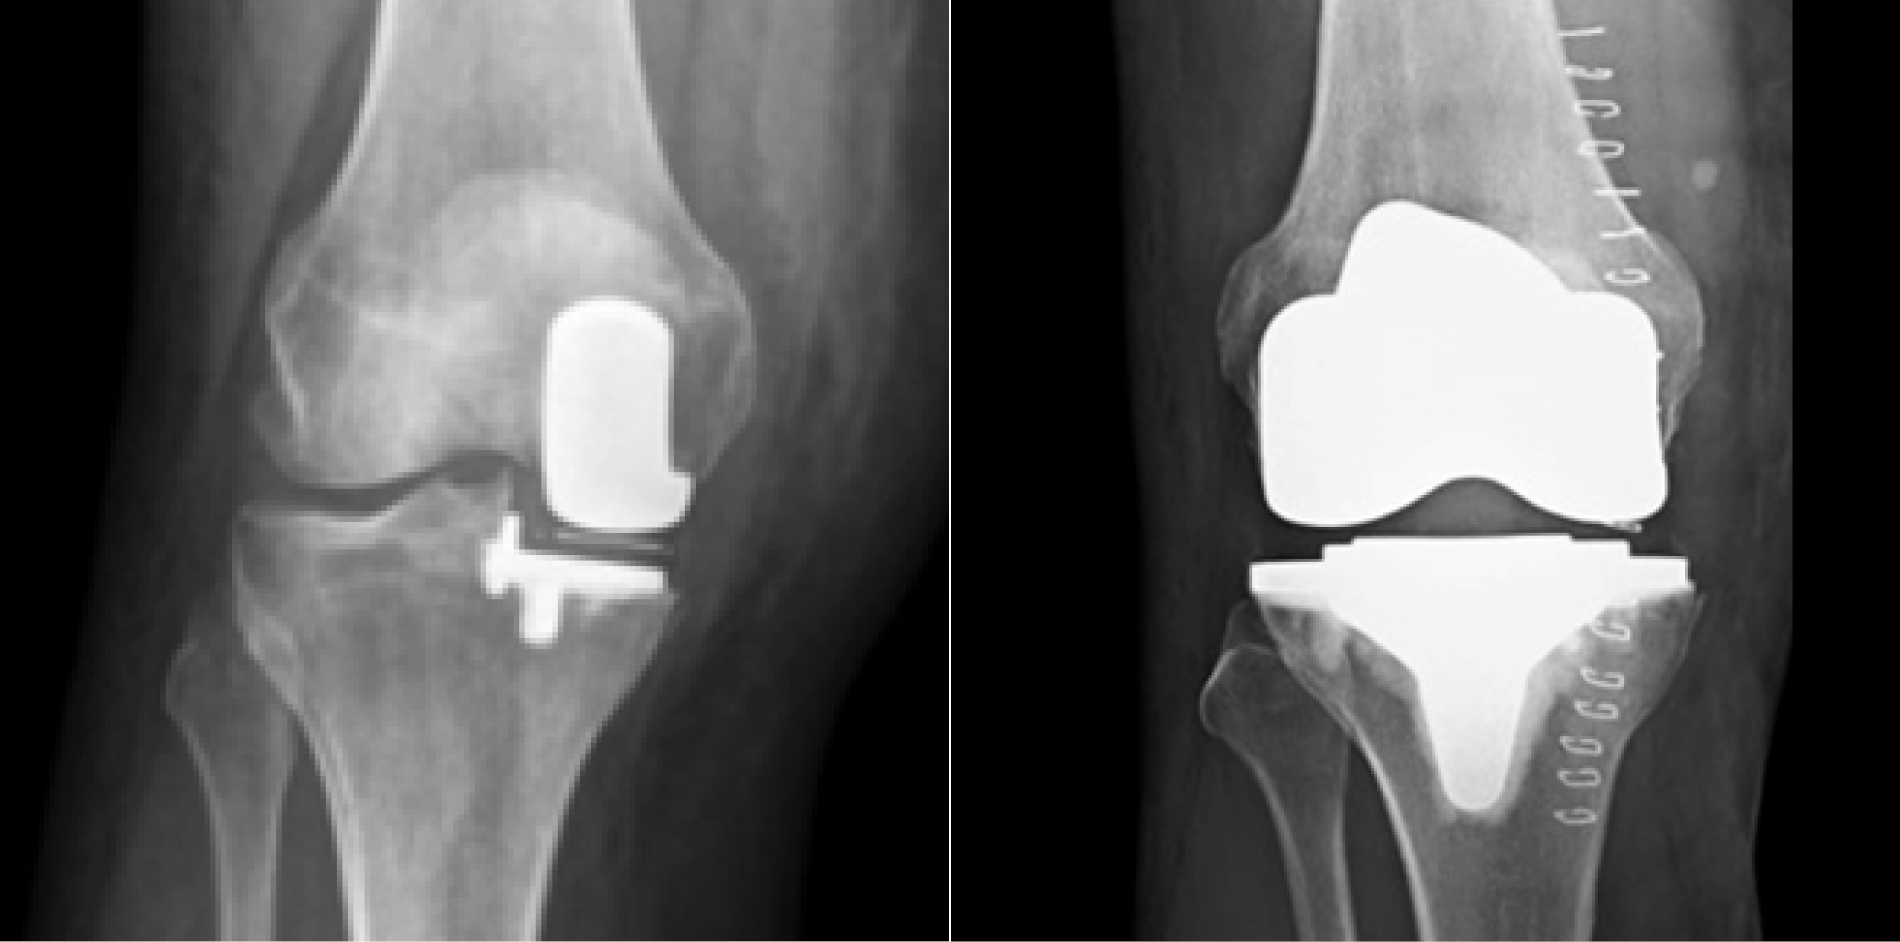

Sind diese Möglichkeiten ausgeschöpft und bestehen weiterhin starke Beschwerden, kann ein operativer Gelenkersatz in Betracht gezogen werden. Je nach Ausbreitung der Arthrose erfolgt entweder ein Teilersatz des Kniegelenks (unikondyläre Schlittenprothese) oder ein vollständiger Ersatz in Form einer Totalendoprothese (TEP).

Dr. med. Matthias Eppinger verfügt über langjährige Erfahrung in der Implantation von Knieprothesen. In komplexen Fällen wird mit patientenspezifischer Instrumentierung gearbeitet, basierend auf individuellen 3D-Knochenmodellen und speziell angefertigten Schnittblöcken.